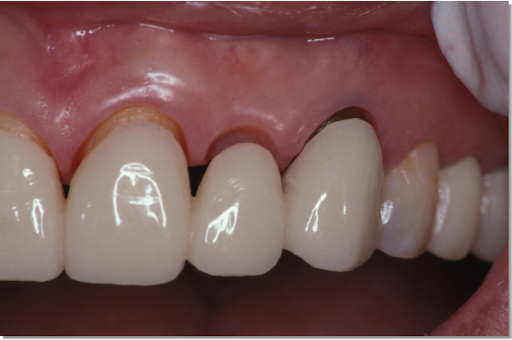

| 治療内容 | 全顎的に歯周病、歯列不正が認められるため、歯周外科を含む歯周治療、矯正治療、インプラント治療、セラミックによる補綴治療後メインテナンスに移行 |